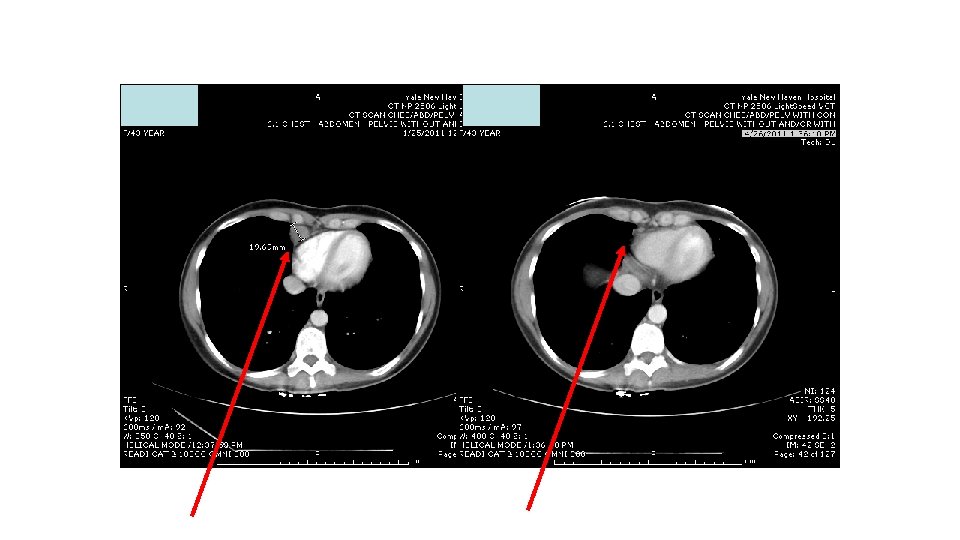

Response to ipi/anti-PD 1, 3/1 dose level